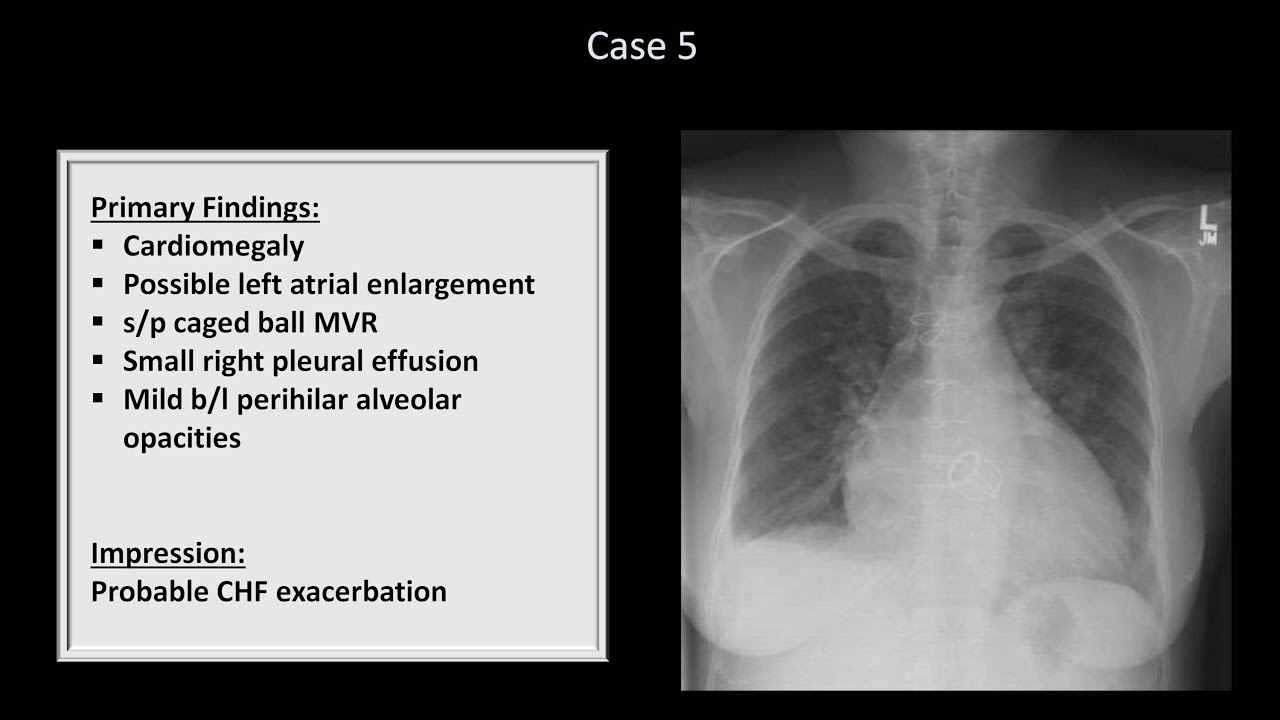

How To Interpret A Chest X Ray Lesson 10 Self Assessment Part 2

How To Interpret A Chest X Ray Lesson 10 Self Assessment Part 1

How To Interpret A Chest X Ray Lesson 10 Self Assessment Part 1